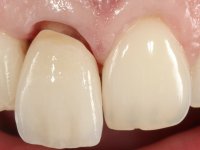

The treatment began with the placement of an intraradicular post and the creation of a new composite resin restoration. This procedure was performed with a surgical approach that allowed the remaining margins to be completely exposed, which were shown to be at a very infra-gingival level. Simultaneously, the periodontal pocket was curetted and root scaling and root planning of adjacent teeth were performed. Two months after this first intervention, the making of the crown began. A pre-print on silicone was performed to make a temporary crown with dual-cured composite resin. Gingival retraction was performed using the technique of kaolin paste compressed by the provisional crown. The impression was made using the double-mix technique with double viscosity with quick-setting silicone. In the laboratory, a crown with a ceramic-coated Zr infrastructure was made. The crown slightly overlapped tooth 12, allowing a dimensionally mimicry of the symmetrical tooth. Its fit was confirmed and approved by the patient; it was definitively cemented with resin-reinforced glass ionomer cement.